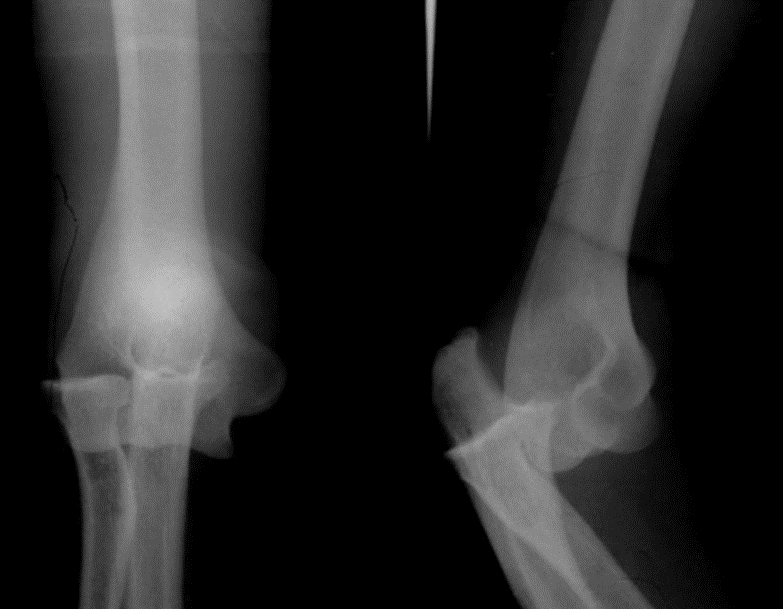

接下来看腿股骨颈骨折是60岁以上老人摔倒时常发生的骨折类型它的临床表现很容易和髋关节脱位混淆所以让我们来看看他们的临床表现有什么不同呢股骨颈骨折受伤后髋部出现疼痛,不能站立或行走,最明显表现是短缩、内收、外旋畸形。

而髋关节脱位,上节课学习过,多发生在交通事故,大家可以看看,当人在座椅上没有绑安全带的情况下,当发生撞击时,膝盖受到暴力作用,使股骨头从后关节囊薄弱处脱出。

主要的临床表现有患髋疼痛、活动受限,被动活动时加剧。患肢出现短缩,髋关节呈屈曲、内收、内旋畸形。来,大家来找茬!把股骨颈骨折和髋关节脱位的表现找出差别。你找到了吗?对,就只有一字之差,股骨颈骨折是外旋,而髋关节脱位时内旋。大家再来看看图片,这样大家是否更能记住了呢?